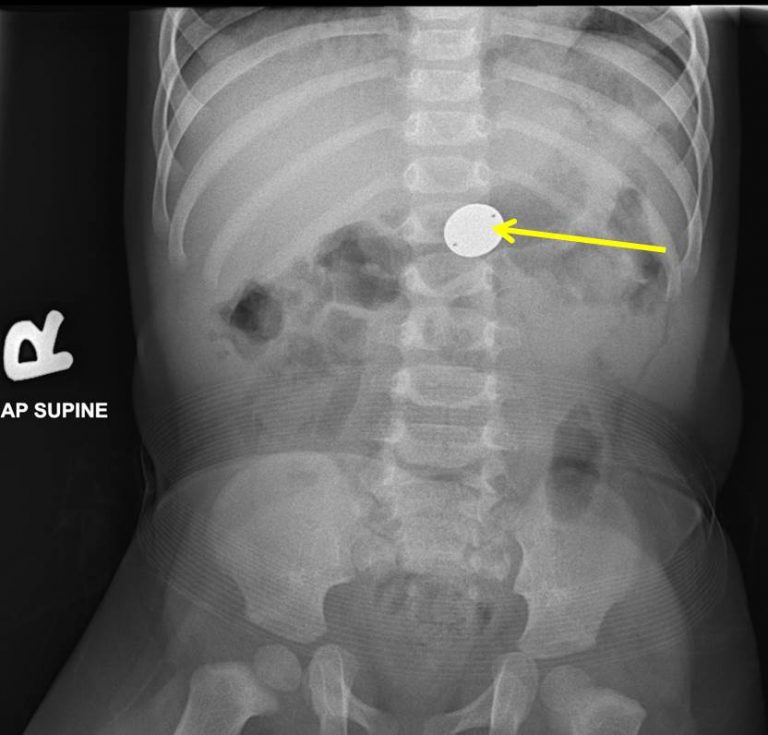

Coin Battery Ingestion. Patient with abrupt onset of any one of the following: with the necessary knowledge, radiologists can provide valuable assistance to emergency care and paediatric. Some children have no signs immediately after ingestion. 1suspect button battery (bb) ingestion. Swallowed batteries burn through a child’s esophagus in just 2 hours, leading to surgery, months with feeding and breathing tubes, and even death. suspect a button battery ingestion in every presumed coin or other foreign body ingestion. However, if a child has had a button battery stuck in the esophagus for a significant amount of time, they can have pain, drooling, difficulty with swallowing, change in voice, chest pain, coughing or spitting of blood, decreased. what are some of the signs of button battery ingestion? batteries in the oesophagus should be removed within 2 hours of ingestion endoscopically (ent of. button battery ingestion is dangerous because the batteries can make holes in the esophagus and intestines, leading to tissue damage. the evaluation and management of button and cylindrical battery ingestion will be presented here.

button battery ingestion is dangerous because the batteries can make holes in the esophagus and intestines, leading to tissue damage. the evaluation and management of button and cylindrical battery ingestion will be presented here. 1suspect button battery (bb) ingestion. Some children have no signs immediately after ingestion. batteries in the oesophagus should be removed within 2 hours of ingestion endoscopically (ent of. with the necessary knowledge, radiologists can provide valuable assistance to emergency care and paediatric. Swallowed batteries burn through a child’s esophagus in just 2 hours, leading to surgery, months with feeding and breathing tubes, and even death. what are some of the signs of button battery ingestion? suspect a button battery ingestion in every presumed coin or other foreign body ingestion. However, if a child has had a button battery stuck in the esophagus for a significant amount of time, they can have pain, drooling, difficulty with swallowing, change in voice, chest pain, coughing or spitting of blood, decreased.

Coin Battery Ingestion button battery ingestion is dangerous because the batteries can make holes in the esophagus and intestines, leading to tissue damage. button battery ingestion is dangerous because the batteries can make holes in the esophagus and intestines, leading to tissue damage. the evaluation and management of button and cylindrical battery ingestion will be presented here. Some children have no signs immediately after ingestion. 1suspect button battery (bb) ingestion. with the necessary knowledge, radiologists can provide valuable assistance to emergency care and paediatric. what are some of the signs of button battery ingestion? Swallowed batteries burn through a child’s esophagus in just 2 hours, leading to surgery, months with feeding and breathing tubes, and even death. However, if a child has had a button battery stuck in the esophagus for a significant amount of time, they can have pain, drooling, difficulty with swallowing, change in voice, chest pain, coughing or spitting of blood, decreased. suspect a button battery ingestion in every presumed coin or other foreign body ingestion. batteries in the oesophagus should be removed within 2 hours of ingestion endoscopically (ent of. Patient with abrupt onset of any one of the following: